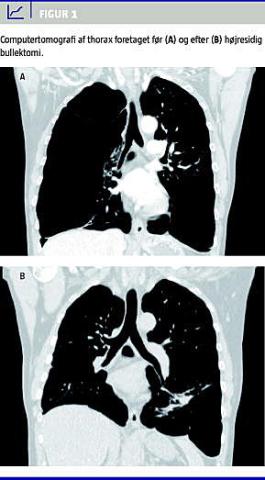

En udredning fem år tidligere pga. produktiv hoste og træthed viste bullae og let nedsat lungefunktion (Tabel 1 ). Mistanken om malignitet blev afkræftet, og pga. begrænsede symptomer blev der ikke foretaget yderligere udredning. I den mellemliggende periode var der imidlertid tilkommet progredierende dyspnø. I overensstemmelse hermed afslørede en computertomografi af thorax (CTt) efter drænanlæggelse betydelig progression af bilaterale emfysematiske bullae med højresidig overvægt og basale kompressionsatelektaser (Figur 1 ). En LFU viste svær obstruktiv lungesygdom (Tabel 1). Ved en regional lungeskintigrafi sås nedsat funktion af højre lunge apikalt (perfusion og ventilation på højre lunge var hhv. 29% og 46%, i øvre lungefelt hhv. 5% og 12% uden mismatch ) og nedsat diffusionskapacitet (34% af forventet, volumenkorrigeret 55%). En A-punktur viste diskret hypoksi (p a O 2 9,1 kPa, p a CO 2 4,3 kPa, pH var 7,42). Efter konference med Rigshospitalet, hvor lungevolumenreducerende kirurgi er centraliseret, aftaltes operation lokalt.

En LFU 3 mdr. senere viste en markant forbedring (Tabel 1), og tilsvarende sås på CTt ekspansion af tidligere konsolideret højresidigt lungevæv (Figur 1).